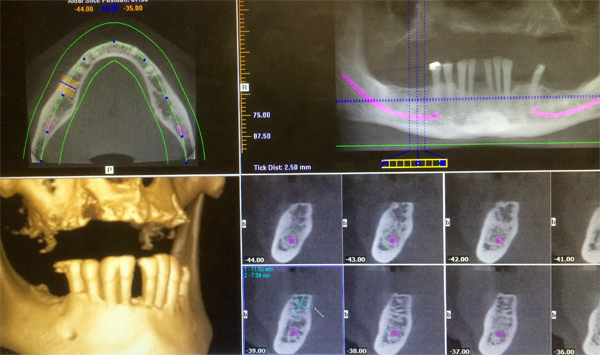

Cone Bean CT Scan imaging for dental implant planning

CT scanning currently represents the gold standard for dental imaging. In recent years, dental technology has moved forward dramatically. CT scans were once the job of hospitals: large, loud and cumbersome machines. CT scans are now frequently used in dental treatments to ensure accuracy for dental implants and give the highest chance of success due to a high level of detail and an ability to precisely plot implant location.

- A low level of radiation is emitted to take a very detailed 3D x-ray of your mouth in just a few seconds.

- The resulting image is uploaded to a software program to accurately plot where implants will be placed in your mouth.

Implant placement is executed with the highest certainty of success.